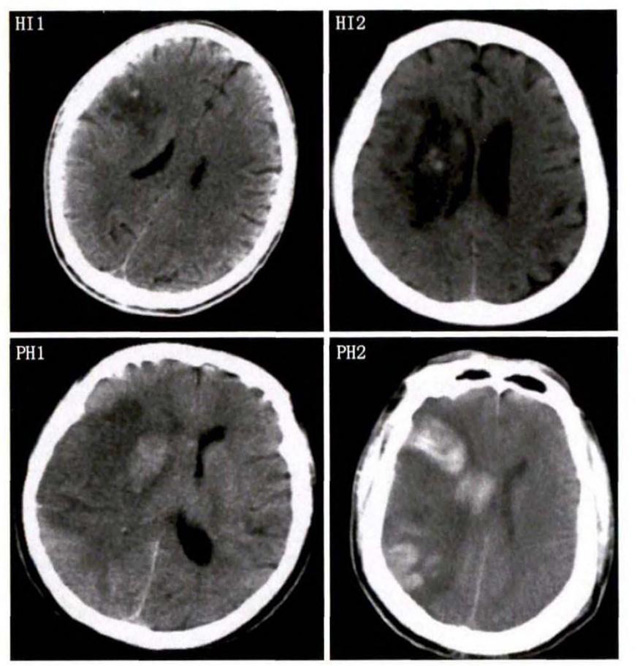

中、老年病患,有动脉粥样硬化及高血压病等脑卒中的危险因素,发病结合神经系统症状和体征,应当考虑急性脑梗死的可能。再经脑CT/MRI发现梗死灶,或排除脑出血、炎症性疾病等,诊断即可确定。脑梗死有时颇似小量脑出血的临床表现。脑栓塞在任何年龄都可以有发病的风险,可以在几秒到几分钟达到顶峰。会有偏瘫不能说话等局部神经功能损坏。栓子来源很种,可能是冠心病、心肌梗塞、心内膜炎等。合并心房纤颤,结合其他脏器官的支持诊断,CT跟磁共振都可以检查确定栓塞位置数量还有是不是有伴发出血等问题。可以帮助诊断。

中老年有高血压糖尿病发病病史,起病神经功能缺损症状,临床表现为腔隙综合征,即可初步诊断本病。如果CT或磁共振证实有与神经功能缺失一致的脑部腔隙病灶, 符合大脑半球或脑干深部的小穿通动脉病变,即可明确诊断。少数患者隐匿起病,无明显临床症状,在影像学检查时发现。

中老年患者,多有高血压病史,情绪激动发病,神经功能缺损症状、头痛、呕吐、颅高压症状,脑出血的可能,CT或者磁共振的检查,可以迅速明确诊断。蛛网膜下腔出血的诊断依据有哪些?突然的头疼剧烈,有恶性呕吐现象,脑膜刺激征阳性,有意识障碍。无局灶性神经系统体征,那么有可能是蛛网膜下腔出血。CT或者磁共振证实蛛网膜下隙高密度征象或血性脑脊液等可临床确诊。